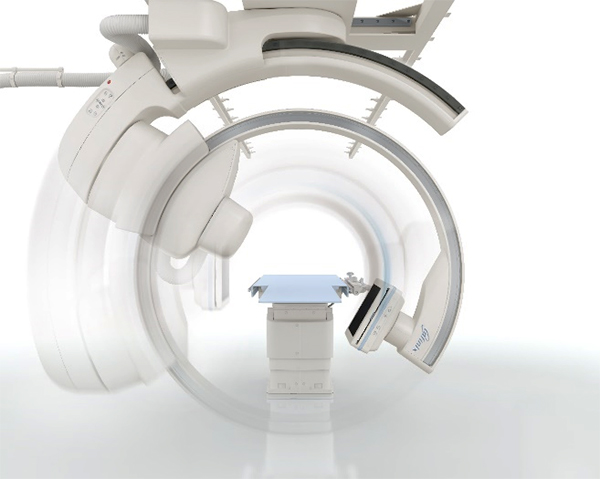

Ця ангіографічна система з кріпленням на стелі спеціально розроблена для використання в операційній кімнаті. С-арка інтегрується з операційним столом та встановлюється в операційній.

Система зі стельовим кріпленням розроблена з урахуванням використання ламінарного потоку.

Широкі інтервали між стельовими рейками дозволяють забезпечити гігієнічні умови експлуатації.

Система Alphenix Hybrid+ (в основі якої система Sky+) має унікальну конструкцію подвійної С-арки, завдяки цьому забезпечується:

Завдяки ізоцентричному обертанню система Alphenix Hybrid+ забезпечує неперевершений доступ та покриття навіть при найскладніших втручаннях. Подвійна конструкція С-арки з можливістю обертанням як справа, так і зліва від пацієнта з найбільшою швидкістю дозволяє скоротити час затримки дихання, зменшити кількість контрасту та отримати бездоганний 3D об'єм від голови до п’ят без необхідності переміщувати пацієнта: